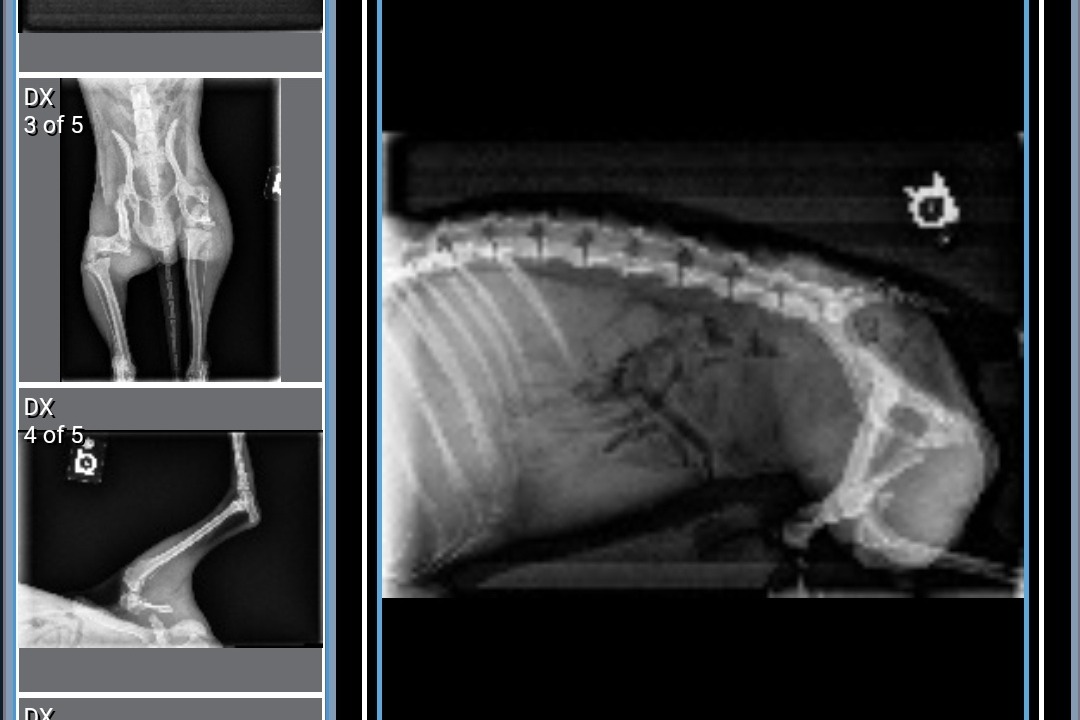

After x-rays, we found out that Mikko had two broken legs. One was an older fracture that had healed improperly and the other was more recent, his leg was completely detached and scraping against his muscle. Due to the fractures, Mikko suffered extensive muscle atrophy and has had to rely on his front legs for mobility. The doctors advised us to proceed with the surgery as soon as possible, stating, "There's still a chance to save his legs but if we wait, we will have to amputate."

The following images are Mikko's x-rays and the first documented photo of him when he was found.